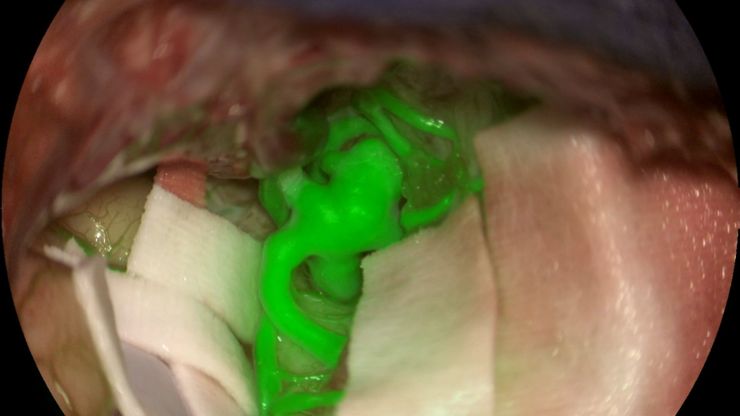

GLOW800 Augmented Reality Fluorescence in Aneurysm Treatment

This case study from Prof. Dr. Feres Chaddad talks about the treatment of unruptured MCA (middle cerebral artery) and PCOM (posterior communicating artery) aneurysms with microsurgical clipping. It…

How AR Fluorescence Imaging Supports Neurovascular Surgery

In this article, we explain how fluorescence imaging works in vascular neurosurgery and explain the benefits of the GLOW800 Augmented Reality fluorescence application.